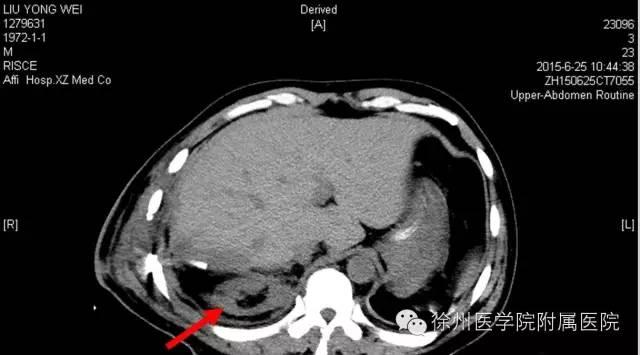

该声明称,患者手术时间是2015年6月20日,术后分别于2015年6月21日(术后第1天)和6月25日(术后第5天)的2次CT复查均显示该患者的右肾存在。

图二 2015年6月25日(术后第5天)CT,右肾如箭头所示。